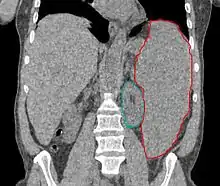

Spleen

- Splenomegaly

- Multiple causes: inflammation/infection (increase in white pulp), congestive expansion (increase in red pulp), increased blood pool, increased macrophage activity, proliferative cellular infiltration, extramedullary hematopoiesis, storage diseases, cysts, solid tumors (primary rare, solitary met from colorectal, ovarian)

- Patients should be continuously monitored, and fields adjusted with shrinking spleen